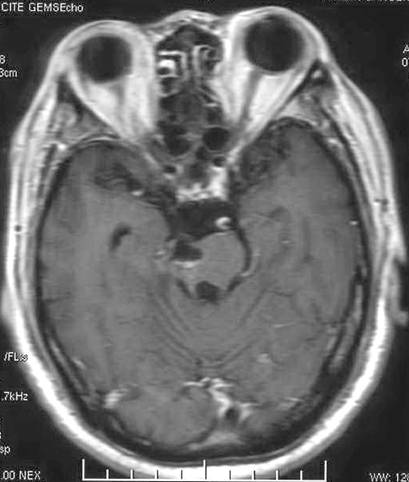

天幕脑膜瘤:

治疗前

治疗后